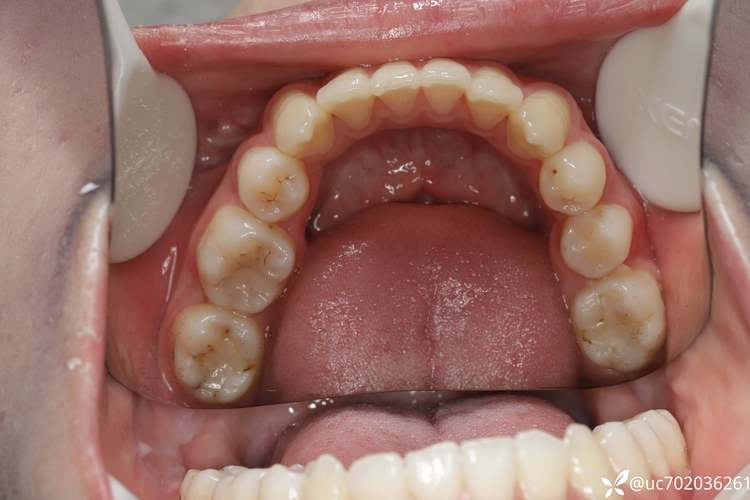

临床表现涉及牙齿、颌骨及面部软组织多个层面,牙齿层面,最典型的是上颌前牙唇倾、深覆盖(上前牙切端至下前牙唇面的水平距离超过3mm),常伴有深覆颌(上前牙切端覆盖下前牙冠长度1/3以上),磨牙呈完全远中或远中尖对尖关系;部分患者可能出现上牙弓狭窄、牙列拥挤,颌骨层面,上颌骨可能发育正常或前突,下颌骨发育不足,表现为下颌后缩、颏部后缩,侧面观面下1/3高度不足,下颌平面角可能增大或正常,软组织层面,患者常表现为鼻唇沟加深、上唇短缩、上唇相对于下唇前突,微笑时可能露龈,颏唇沟变浅,严重者可出现“鸟嘴”样面型,功能层面,由于咬合关系异常,咀嚼效率降低,长期可能引发颞下颌关节弹响、疼痛,甚至肌肉疲劳。

诊断需结合临床检查与影像学分析,临床检查包括面部软组织评估(观察正面对称性、侧面凸度、唇部位置等)、口腔内检查(记录牙齿排列、磨牙关系、覆颌覆盖、中线情况、牙弓形态等)及功能检查(咀嚼肌触诊、颞下颌关节活动度检查),影像学检查中,X线头影测量是核心手段,通过测量骨骼指标(如SNA角反映上颌相对于颅底的位置,正常82°±3°,SNA角增大提示上颌前突;SNB角反映下颌相对于颅底的位置,正常80°±3°,SNB角减小提示下颌后缩;ANB角反映上下颌骨关系,正常2°±2°,ANB角增大>4°为典型的二类骨骼关系)、牙齿指标(如U1-SN角反映上颌中切牙倾斜度,正常105°±8°,过大提示前牙唇倾;L1-MP角反映下颌中切牙倾斜度,正常97°±7°,过小提示下牙舌倾)及软组织指标(如上唇突度、颏唇沟深度等),综合判断错颌畸形的骨骼与牙齿成分,常用头影测量指标及意义如下表所示: